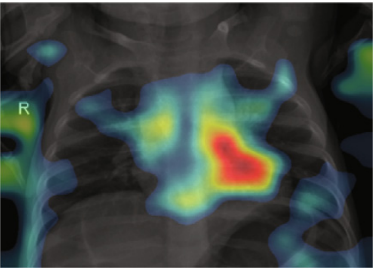

4.3 Domain experts’ evaluation of XAI methods

In most of the reviewed studies, the application of XAI comes down to the series of colorful images without any assessment about how valid these explanations are. Colored explanations obscure the original image, which makes it even more difficult to assess their correctness. In images with XAI heat maps, it is often hard or impossible to see pathologies and guess if the model works well. Raw lung images shall be put next to explanations. Also the explanations should be interpreted or validated by radiologists. Otherwise, they are redundant and contribute nothing to the trustworthiness of the model.

Together with the radiologists, we analyzed the explanations from the discussed works. In the following paragraphs, we discuss the most common mistakes or inappropriate explanations.

In the first example, in Figure 5a), the model focuses on clavicles, scapulas, and soft tissues, which are outside the lungs. Very likely, the model predicts illness based on an improper part of the image. Location of the areas marked by explanation should be inside the chest on the lung tissue because COVID/̄19 lesions are not located on, e.g., lymph nodes. Moreover, there are some elements that cannot be considered as decision factors like imaging artifacts (cables, breathing tubes, image compression) or embedded markup symbols [37]. To prevent the model from focusing on irrelevant features, in some studies, the lungs were segmented, and their background was removed [31, 32, 34, 45, 50]. However, it may not help when some imaging artifacts are present in the area of the lungs.

The second example, in Figure 5b) shows that the model does not take the lesions into account. The model states that parts of the lungs other than the ones marked by the radiologist are relevant for model prediction. Explanations that “roughly indicate the infection location” [32] are not acceptable for the robust model. The model should do this with the accuracy of the pixel marked by radiologists as relevant.

The third example, in Figure 5c), visualization is not clear. The study describes a different XAI method than the one present in the image. Moreover, this visualization highlights the whole image, and it is not possible to guess which features took part in the prediction. It is important to point out that some explanation methods can give clearer results for a specific type of DNN and for a specific domain.

The last example, in Figure 5d) is blurred. The image of the lungs is improperly taken, and the process should be repeated. The current image is useless for the accurate diagnosis process. Such images should be removed during data resource verification before model training.

Evaluation of explanation methods is crucial for confirmation of model trustworthiness. First of all, radiologists should validate a specific model with the help of XAI. They should assess location, size, and shape of marked regions by explanation methods. Their interpretations should contain clear references to structures and lesions in the lungs, such as posterior basal segment, ground-glass opacity, consolidation, frosted glass shadows, etc. The example of a well-prepared XAI interpretation can be found in the study [30].